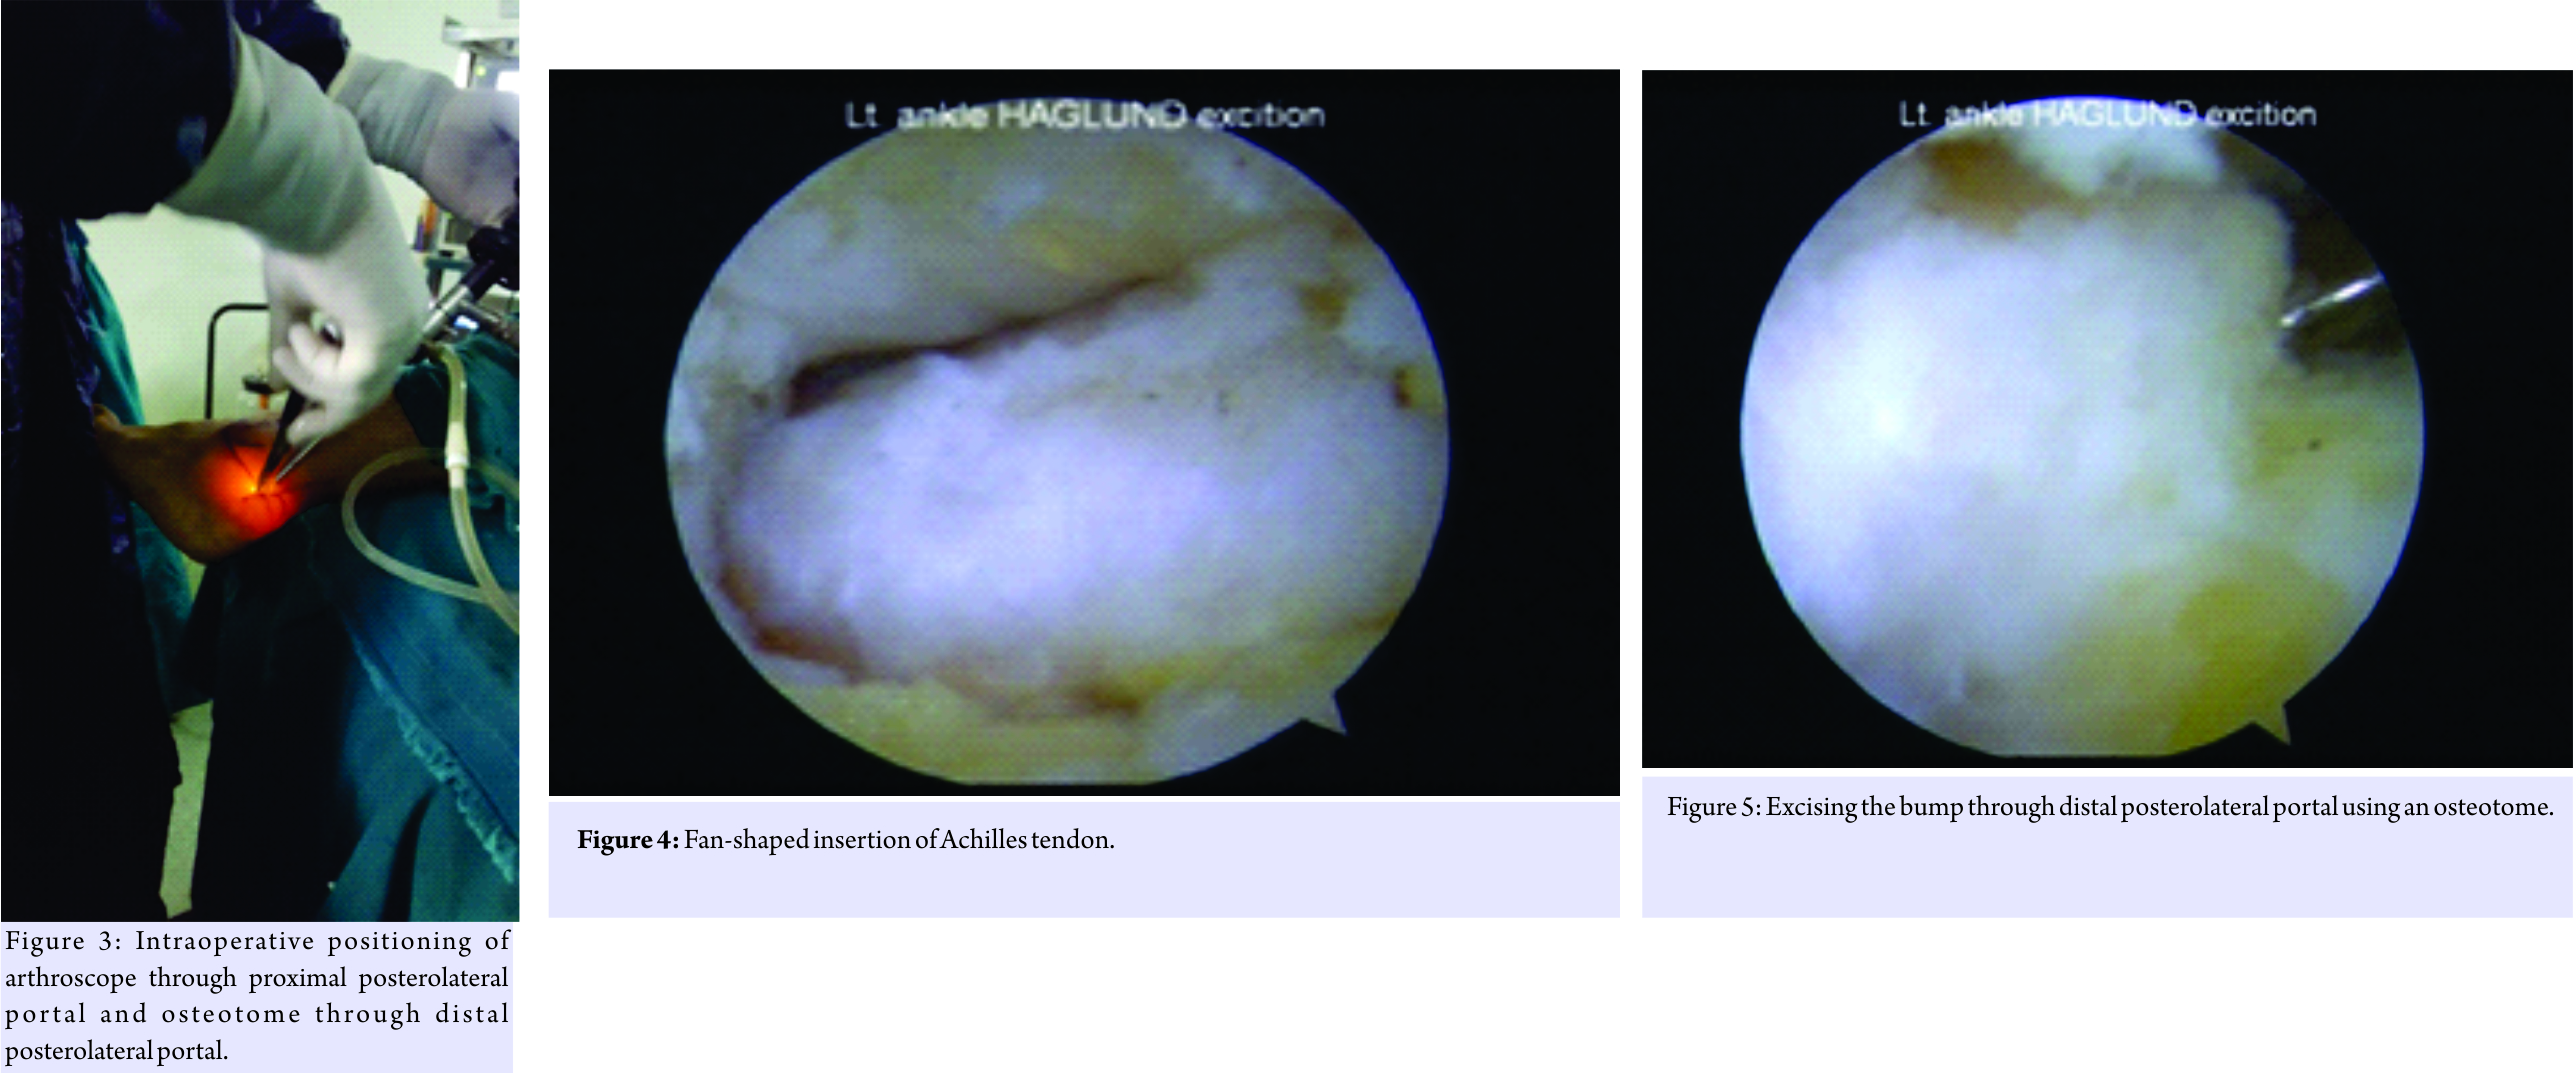

The patient is a 40-year-old male patient with moderate obesity complaining of pain and swelling in the left retrocalcaneal region. X-ray and USG of ankle were taken and diagnosed having Haglund’s bump with retrocalcaneal bursitis, calcification in tendon is ruled out by USG. He was given 6 months of conservative treatment, but there was no improvement. His American Orthopaedic Foot and Ankle Society (AOFAS) score was 64 and Fowler- Philip angle is 71 (Fig. 1). Surgical intervention was planned. Surgical technique: The patient in spinal anesthesia is placed in lateral decubitus position. Tourniquet is placed in the thigh and the other limb is flexed at hip and knee so that it will not interfere with the procedure. The limb is scrubbed and draped, tourniquet inflated. Bony landmarks and the portals are marked.

With the ankle in the neutral position, a line was drawn from the tip of the lateral malleolus to the Achilles tendon, parallel to the foot sole. The posterolateral portal was situated just above the line, in front of the Achilles tendon (Fig. 2). A small vertical skin incision is given, blunt trocar was used to reach the retrocalcaneal space and is replaced with 30° 4 mm arthroscope (directing towards 1st web space).

Then, an accessory lateral portal is created by giving a stab incision below the posterolateral portal using a needle as a guide so as to reach the posterolateral corner of the calcaneum. A stab incision is given, spread with mosquito forceps while entering the retrocalcaneal space. The bursa is shaved with a shaver tip facing away from the Achilles tendon. The medial and lateral corners of the Haglund’s bump are viewed after the bursa is shaved off. An osteotome is passed through the accessory lateral portal (Fig. 3) and the Haglund’s bump is removed and is confirmed on fluoroscopy and by plantar flexing the ankle to see whether the sufficient amount has been removed or not. The sharp edges are smoothened using an acromioniser (Fig. 4 and 5). The skin is closed using non-absorbable sutures, and pressure dressing is applied, tourniquet is released (Fig. 6).